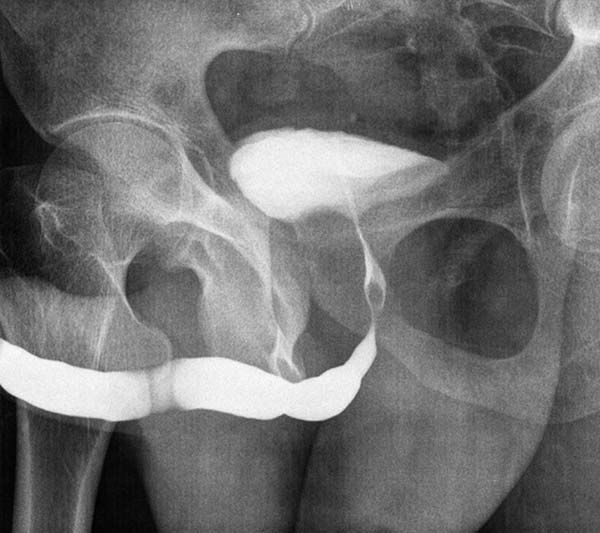

Uretrocistografía

Colocación de sonda vesical y llenado con contraste.

Imágenes fluoroscópicas durante llenado y micción voluntaria.

Determina presencia de reflujo, estrechez o fístulas.